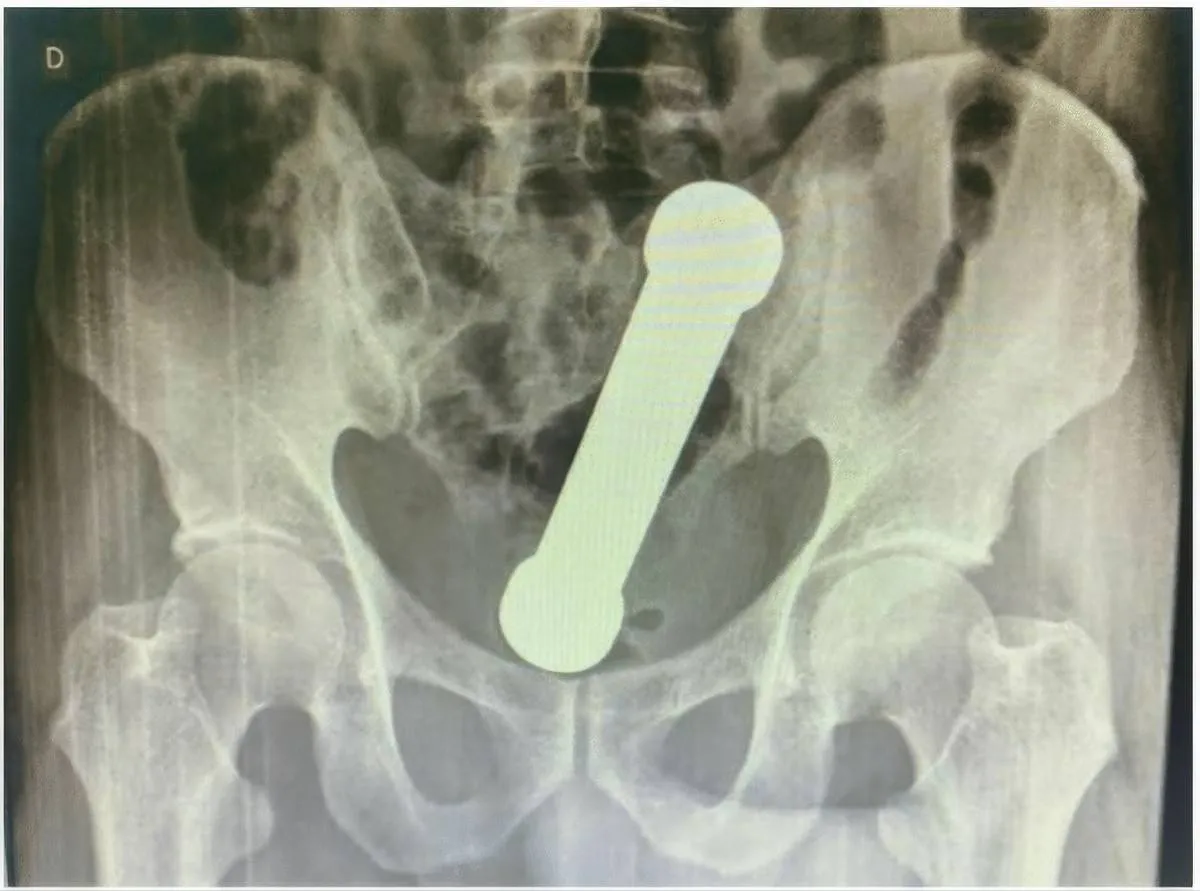

picture_vk_dumbell_brasil_01

Röntgenfoto van het bekken (vooraanzicht) waarop een vreemd voorwerp (halter/dumbbell) te zien is, ongeveer ter hoogte van de overgang van endeldarm naar dikke darm. (Foto: International Journal of Surgery Case Reports)